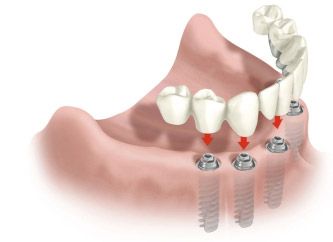

Установка моста на двух имплантатах

Восстановление челюсти на 4-х

или 6-ти имплантатах

Все на четырех или шести имплантах (all on 4 / all on 6)

Восстановление зубов по технологии All on 4 занимает один день. Потребуется внимательно изучить состояние костной ткани и выбрать места для установки 4 имплантатов на которых в тот-же день установят временную челюсть.

Постоянная челюсть фиксируется на имплантаты через 4-6 месяцев, после полного сращивания их с костью.